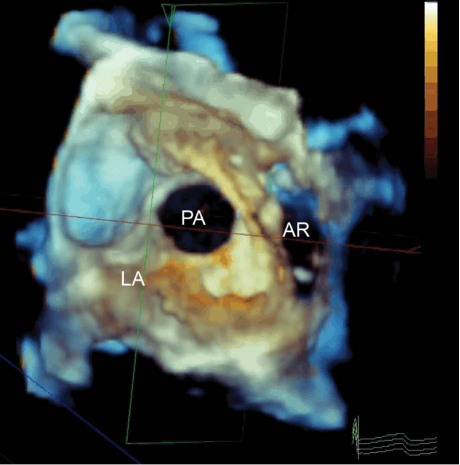

Fig. 2 Multiplanar reconstruction of a 3-dimensional full-volume transesophageal echocardiogram shows a large entry orifice of the pseudoaneurysm (PA)—as viewed from the left atrium (LA)—communicating with the aortic root (AR). The subsequent fistulous connection into the LA itself is not shown. Real-time motion image is available at www.texasheart.org/journal.